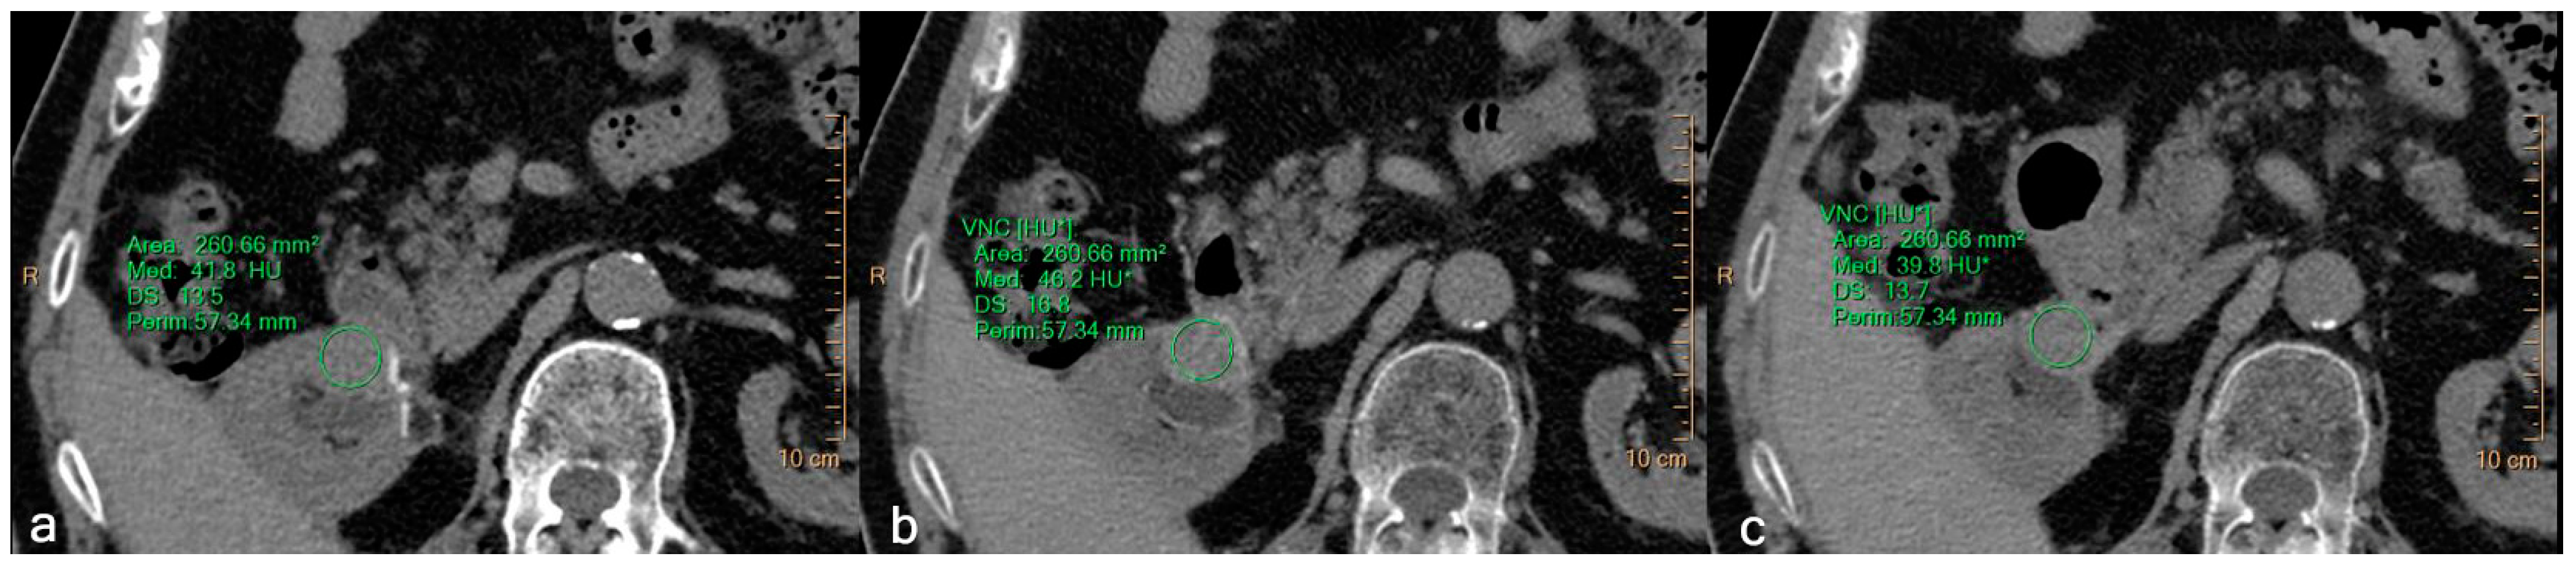

Virtual Non-Contrast Spectral CT in Renal Masses: Is It Time to Discard Conventional Unenhanced Phase?

3. Results

3.2. Quantitative Assessment